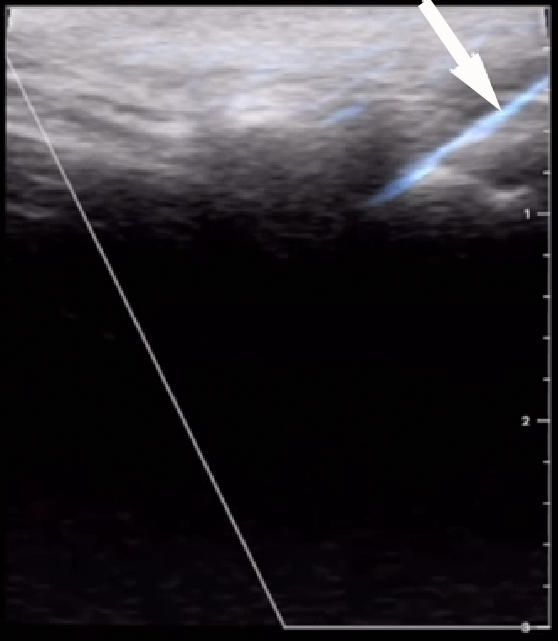

Ultrasound-guided punctures may approach the target (joints, vessels or nerves) from a position perpendicular or parallel to the US beam, referred to as ‘out-of-plane’ and ‘in-plane’, respectively (Figure 4). The in-plane approach enables the operator to visualize the needle shaft and tip, as it is directed toward the target, but it requires skill and may result in a false sense of security, despite having been demonstrated to result in faster and more accurate performance. On the other hand, the out-of-plane technique is more difficult and relies on tissue movement or fluid localization rather than strict needle visibility to confirm its position.46 In the TMJ US-guided injections using the out-of-plane approach, the correct position of the needle is achieved by extending and narrowing the joint space by the infiltration and aspiration of fluid, respectively.19 Champs et al. validated a longitudinal US-guided in-plane approach for TMJ IAI, in which the needle is inserted at an angle of 30°, with the US probe in the preauricular region, approx. 1 cm in front of the tragus, parallel to the mandibular ramus and perpendicular to the zygomatic arch.21 This technique proposes a direct visualization of the needle all the way to the joint with great precision and provides noticeably higher accuracy during puncture.21 Most clinical and cadaveric studies use the coronal route of scanning and in-plane needle insertion (Figure 5),9, 10, 11, 12, 14, 17, 18, 19, 20, 21 whereas other reports did not report these technical details.13, 15, 16

Most articles describing TMJ minimally invasive procedures (and daily clinical practice) are based on washing-out the upper joint space in both the US-guided and blind techniques. Nevertheless, some evidence has demonstrated that IAI directed to the lower or both TMJ spaces has a better effect than IAI into the upper space alone.47 Lower joint space injection is believed to be a difficult procedure because of a narrow space, a small volume and the ‘hidden’ location. The blind technique for lower joint space injection was described by Li et al.47 Clinical information on US-guided IAI into the lower joint space appears to be very limited.20 Levorova et al. reported a technique for US-guided TMJ intra-articular infiltration directed toward the lower joint space (Figure 6).19 Cha et al., in a cadaver-based study, observed that upper joint space injection showed a similar level of success for the blind and US-guided techniques.20 However, for the lower joint space, the US-guided technique had a significantly higher success rate (90% vs. 30%) and the blind technique was associated with a considerable proportion of unsuccessful/inappropriate injections to the lower joint space.20 To date, only 4 controlled CTs that compare the blind and US-guided techniques for TMJ arthrocentesis have been published.9, 10, 11, 12 Two of them used DPA9, 10 and the others used type II SPA11, 12 (the comparison of these studies is presented in Table 1). Şentürk et al., in a CT, reported the longest follow-up (1 year) in a comparison between the blind and US-guided techniques for TMJ arthrocentesis.12 The results show that US guidance is effective in type 2 SPA, as it aids the visualization of the needle during puncture; however, it did not resolve pain or improve the range of motion as compared to the blind technique.12 The clinical effectiveness of US guidance for TMJ arthrocentesis and IAI is mostly analyzed based on 4 aspects: pain reduction; the range of movement; needle positioning (or repositioning) attempts; and the total procedure time. The literature comparing US-guided arthrocentesis vs. the blind technique is scarce. Two systematic reviews have been published recently,23, 24 in which very similar conclusions were reached, since they both selected the same articles for the final analysis.9, 10, 11, 12 Both reviews found no significant differences in pain reduction and the maximum mouth opening, no conclusive results were observed in reducing needle repositioning, and also data on the potential to reduce the procedure time was inconclusive.23, 24 Although achieving access to the joint space occupies most of the surgical time, studies show that the total time is longer in the US-guided procedures, since a US examination itself requires additional time.9 These conclusions are shared by all studies, as some publications suggest that US guidance would improve the precision of needle placement, especially when the lavage of the lower joint space is performed.20 Cadaver-based studies observed that US-guided IAI and arthrocentesis techniques had a higher accuracy when the needle was located inside the joint spaces,20, 21 as they provide the image verification of having punctured the joint space and the real-time screen visualization of the distension of the space after infiltrating fluid.22 Antony et al. observed that the US-guided technique resulted in a significantly greater pain reduction in the immediate postoperative period.10 Bhargava et al. found that in type 2 SPA, US guidance minimized the number of attempts of needle manipulation as well as possible complications, and provided easier access to the upper joint space.11 Additionally, Anthony et al. suggested that in patients with obesity, US-guided arthrocentesis could be more precise in locating the joint spaces, whereas the blind technique arthrocentesis required multiple punctures to achieve successful lavage.10